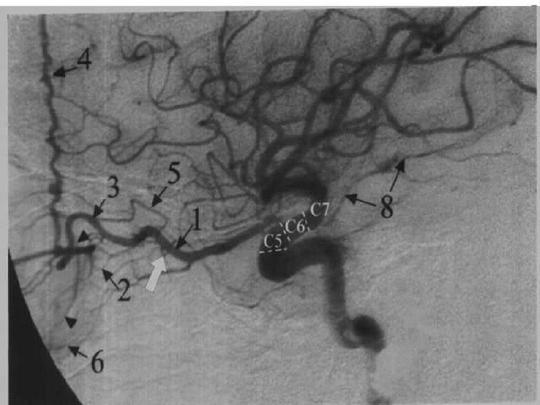

为什么要做全脑血管造影?

静脉曲张血管造影术

2dsa造影下的胸主动脉破裂情况.jpg